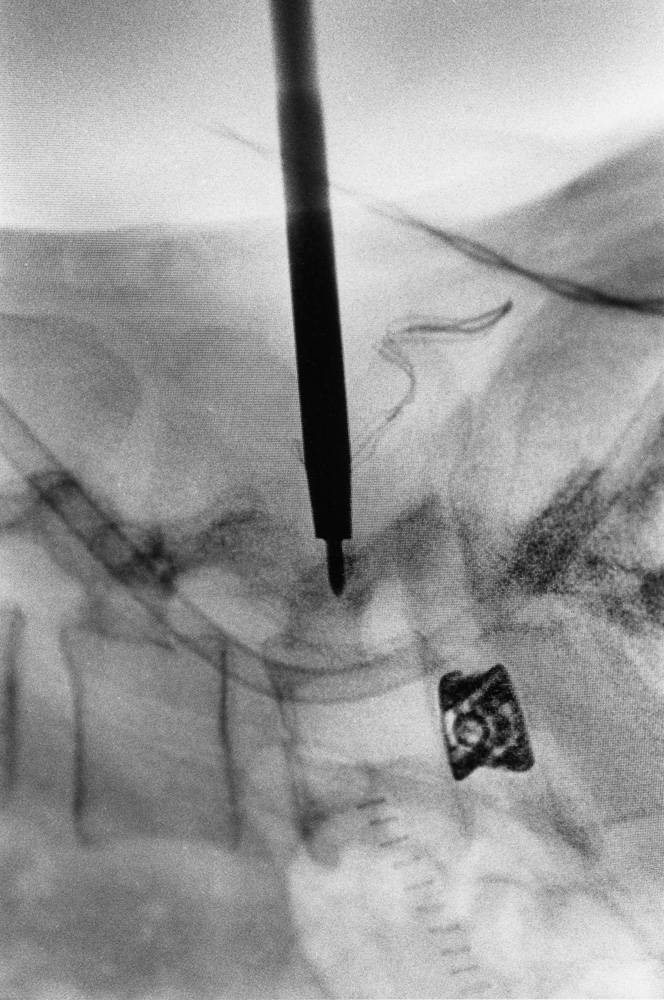

Da metà giugno a fine novembre 2021, Renato D’Agostin e la sua macchina fotografica hanno avuto accesso esclusivo alla clinica: dal centro di riabilitazione alle sale operatorie, dai reparti di degenza all’area amministrativa, dal laboratorio di analisi agli ambulatori.

Il risultato di questo viaggio immersivo nel mondo e negli spazi della struttura sono oggi 20 scatti unici e irripetibili, raccolti in questo catalogo e nella mostra “La Cura.

La clinica Rizzola nelle fotografie di Renato D’Agostin” ospitata presso Spazio Mostre Italvanto Battistella, a San Donà di Piave, dal 7 al 17 gennaio 2022 Gli scatti trovano oggi esposizione permanente all’interno della Casa di Cura Sileno e Anna Rizzola.